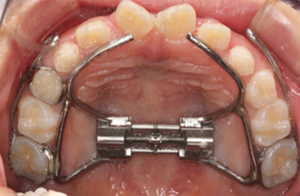

当院では、「急速拡大装置(ハイラックス)」という装置を使用して治療を行っております。

ハイラックスは、上顎骨(鼻上顎複合体)の成長を促進させることができるため、鼻の通りが良くなり、鼻アレルギーや喘息(気道が狭い状態)の緩和、といった効果もあります。

通常は、子どもの矯正で使用される器具ですが、当院では成人矯正の場合にもハイラックスを活用しております。

歯列拡大によって非抜歯矯正の可能性が高くなります。(必ず非抜歯矯正が可能になるとは限りません)

4.上顎急速拡大装置セット

歯面の掃除をした後、実際に装置を装着します。装置の取り扱いを説明し疑問点などを確認します。

とくに、装置の説明や効果などはしっかりご説明しています。